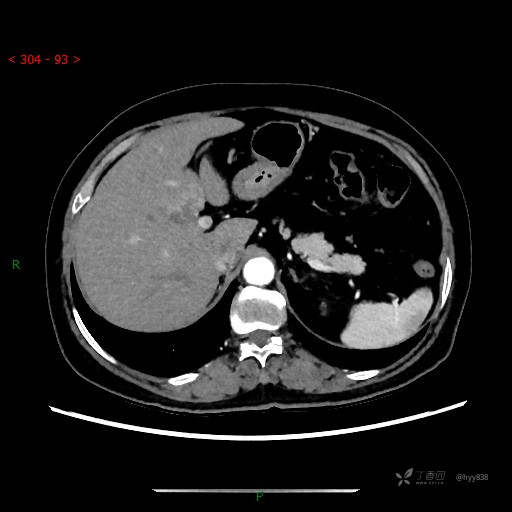

上腹部CT平扫